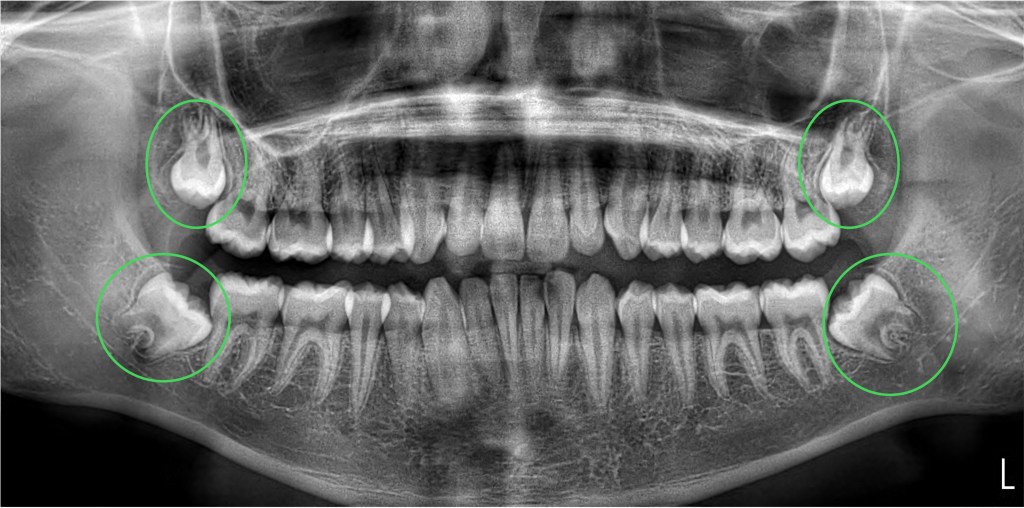

The force that pushes a tooth into the mouth is the formation of the root, which acts like a rocket to propel it, ideally, into the perfect position. The crazy thing is, the longer the roots get, the closer they get to important structures like the sinuses (near top wisdom teeth) and a nerve that gives the feeling to your lower lip and chin (bottom ones). If those roots get super close, touch, or “wrap around” those structures, there is increased risk of damage.

Fortunately injuries to these things are rare, but when they happen, they can be a problem. Here’s what we see on basic x-rays: